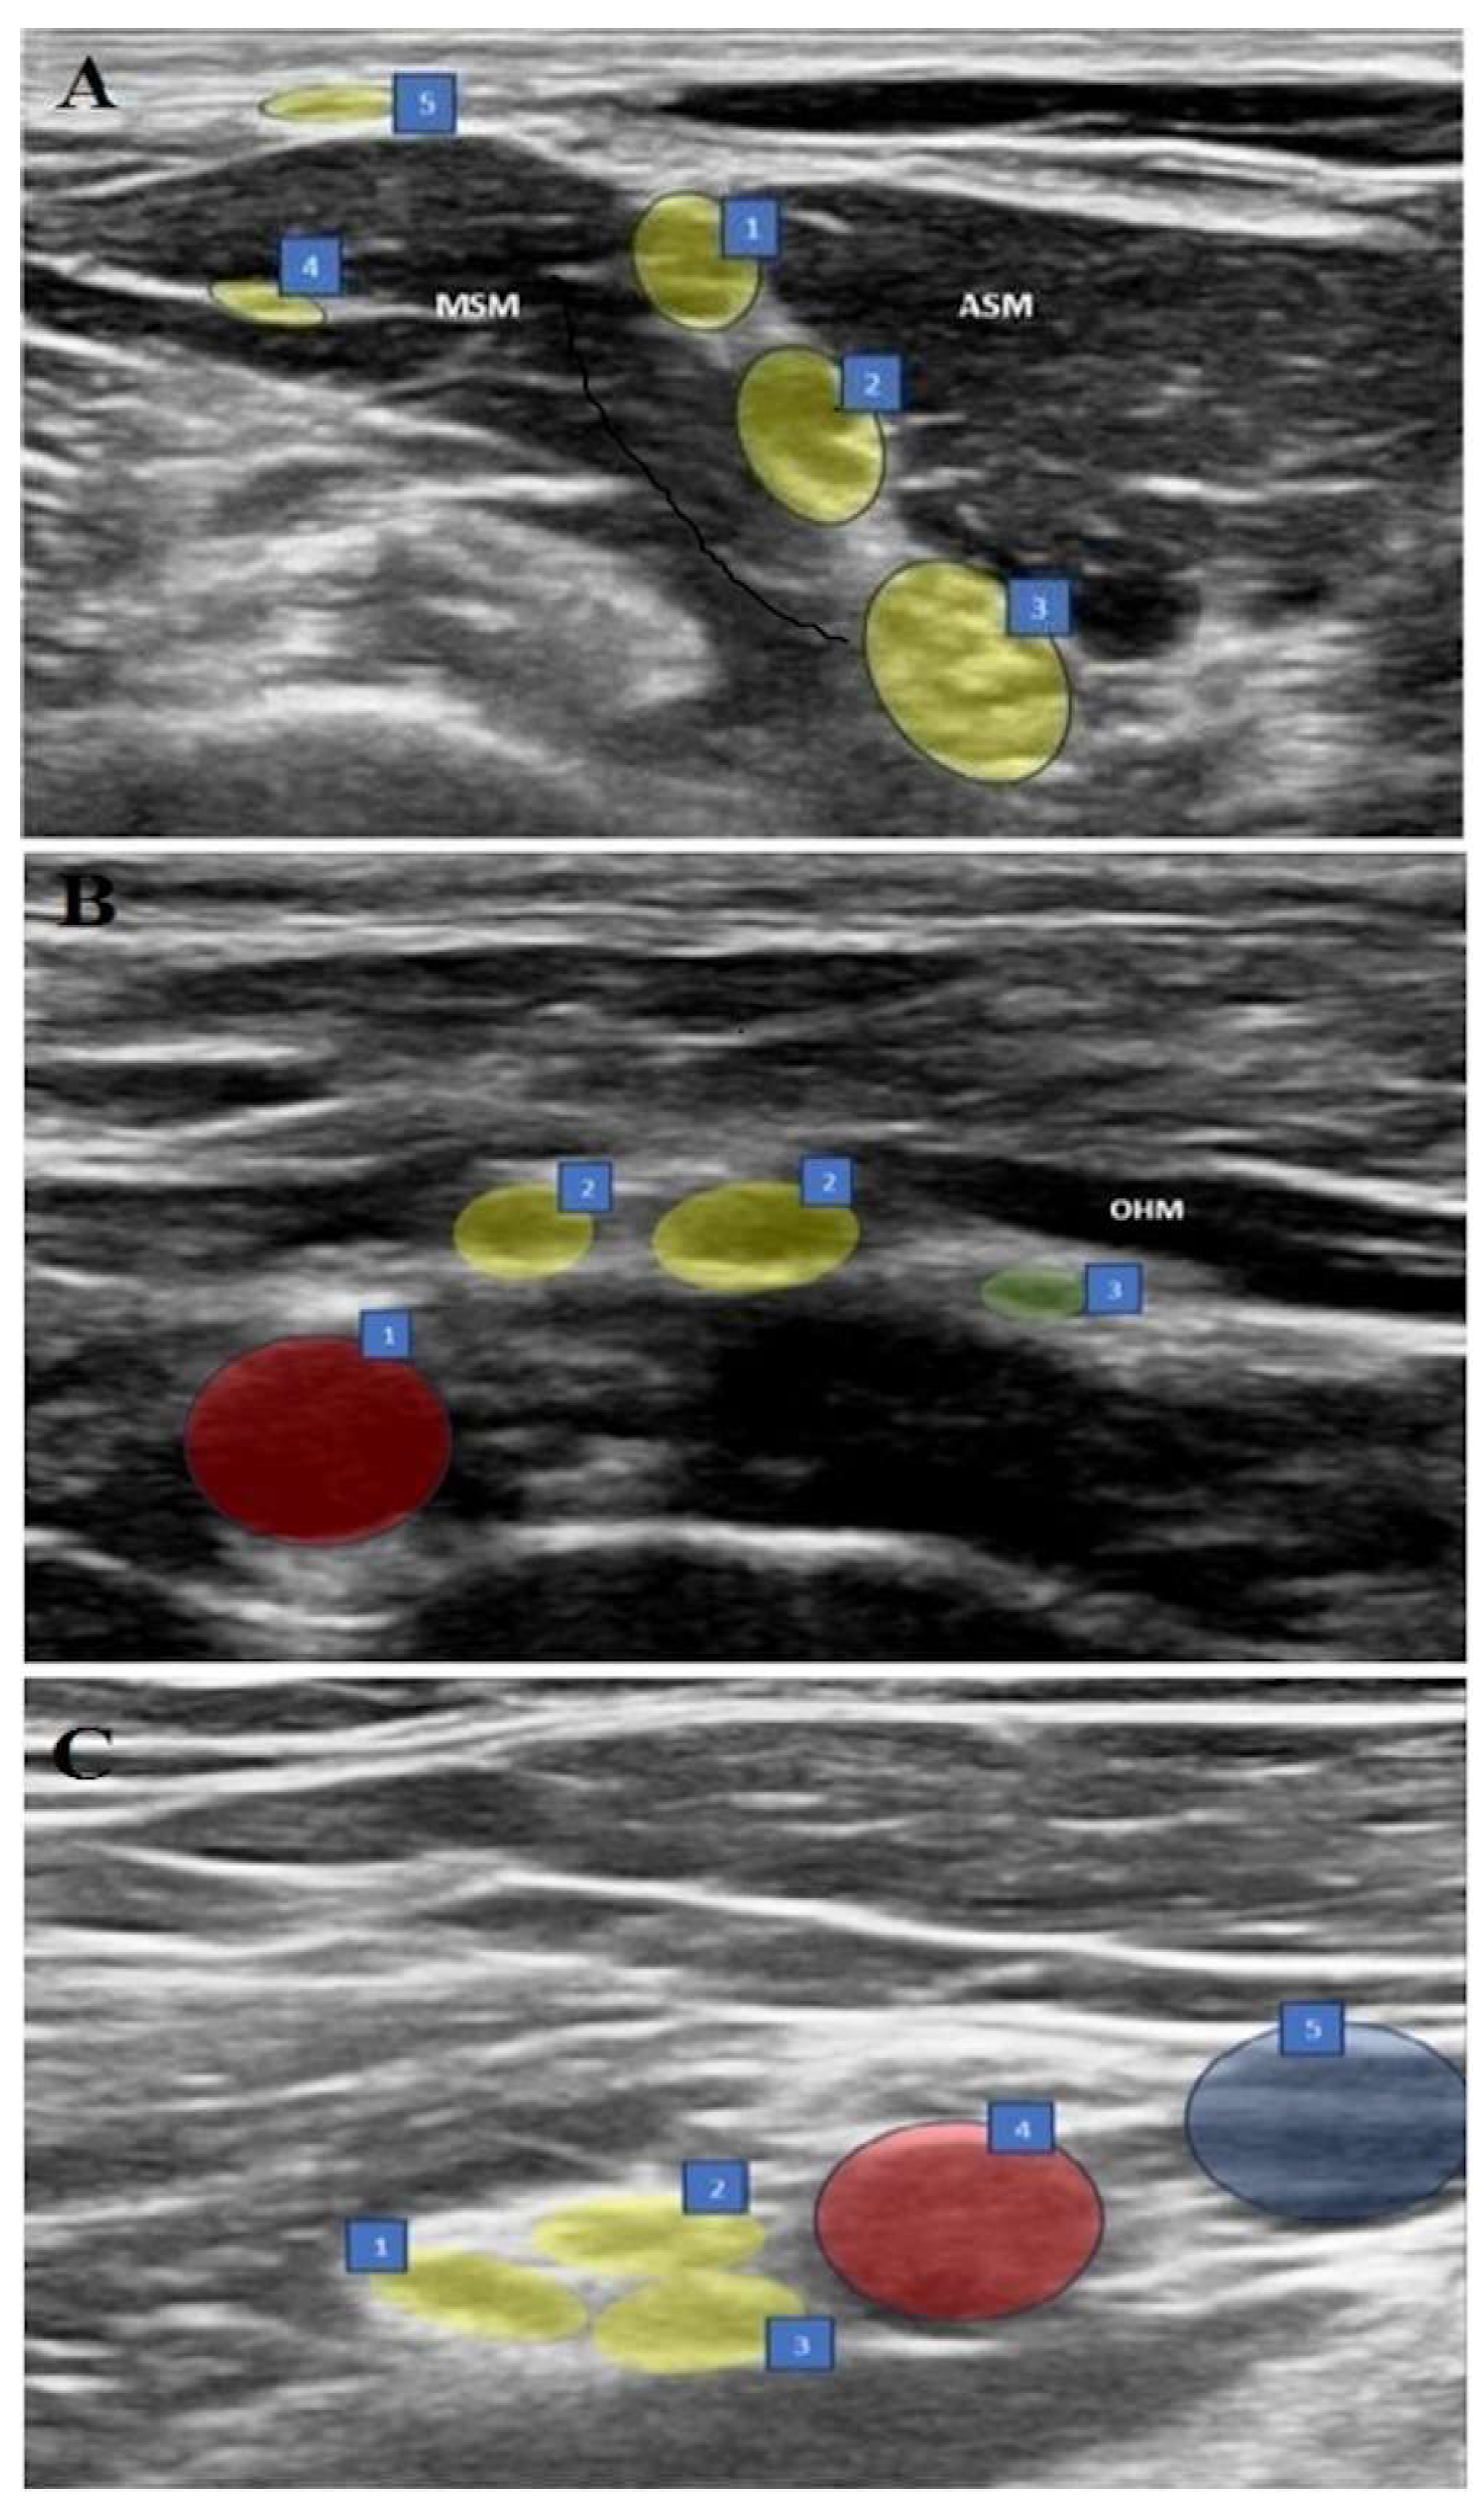

Figure 1. (AC) Sonographic views of three blocks. (A) ISB: 1. C5 nerve root, 2. C6 nerve root, 3. C7 nerve root, 4. Long thoracic nerve, 5. Supraclavicular nerves, ASM: Anterior scalene muscle, MSM: Middle scalene muscle. (B) ASB: 1. Subclavian artery, 2. Upper trunk, 3. Suprascapular nerve, OHM: omohyoid muscle. (C) CCB: 1. Posterior cord, 2. Lateral cord, 3. Medial cord, 4. Axillary artery, 5. Axillary vein.

2.4. Interscalene Brachial Plexus Block (ISB) (Figure 1A)

In the supine position, with the arm adducted, the probe was placed transversely in the supraclavicular fossa just proximal to the midpoint of the clavicle. The brachial plexus was identified as a bright echogenic structure, posterolateral to the subclavian artery (bunch of grapes sign). Then, the nerves were held in the center of the screen, and the probe was moved in a cephalic direction up to the interscalene groove until a “string of pearls” image was obtained of the nerve roots located between the anterior and middle scalene muscles. After optimizing the image of the nerve roots as hypoechoic round or oval structures, the needle was placed posterolateral to the probe and moved in the plane. The needle was then located between the middle scalene muscle and the brachial plexus roots, and 15 mL of 0.25% bupivacaine was slowly injected into the area between the C5-6 roots.

2.5. Anterior Suprascapular Nerve Block (ASB) (Figure 1B)

In the supine position, with the arm adducted, the probe was placed in the supraclavicular fossa to identify the brachial plexus. The plexus was then followed until the suprascapular nerve branching from the upper trunk was seen. The needle was advanced from posterolateral to anteromedial, and the most lateral transverse image of the nerve was obtained with the in-plane technique. The nerve was entered between the superficial cervical fascia and prevertebral fascia under the omohyoid muscle from the lateral side, and 5 mL of 0.25% bupivacaine was injected following hydrodissection with DW5 and negative aspiration.

2.6. Costoclavicular Brachial Plexus Block (CCB) (Figure 1C)

The ipsilateral arm was abducted at 90 degrees with the palm facing the ceiling, and the ultrasound transducer was positioned parallel to the mid-clavicle. The long axis of the transducer was tilted slightly cephalad, and the ultrasound beam was directed into the costoclavicular space. The ultrasound image was optimized so that all three cords of the brachial plexus were seen together lateral to the axillary artery, anteriorly between the clavicular head of the pectoralis major and the subclavius muscle and posteriorly between the serratus anterior muscle overlying the second rib. The needle was then advanced laterally and medially in the plane. With the needle tip in its intended position, a small volume (0.5–1 mL) of DW5 was injected before each injection to ensure that the needle tip was within the hyperechoic connective tissue matrix underlying the brachial plexus sheath and between the cords of the brachial plexus and not intraneurally. After verification, the local anesthetic was injected into multiple sites in 4–5 mL aliquots by redirecting the needle, for a total of 20 mL of 0.25% bupivacaine, to homogeneously distribute the local anesthetic.